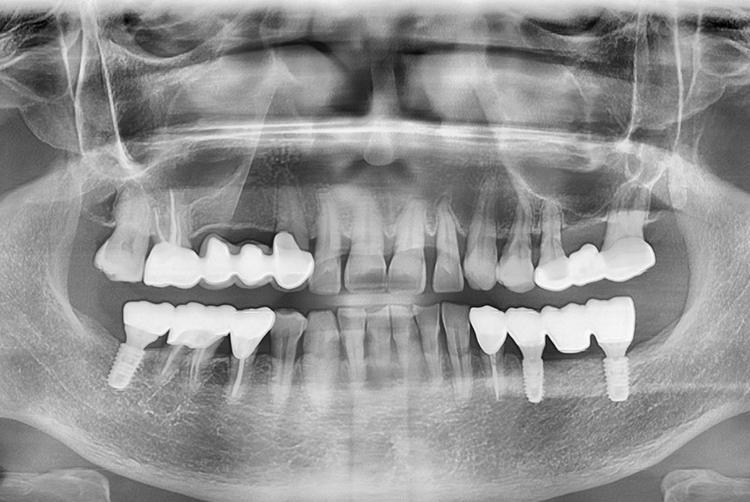

a7acdfae17a51621cddbf040dca37c8a.jpg

치료전 : 2018-12-22